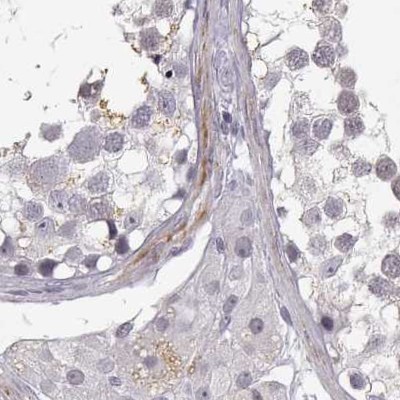

- Immunohistochemistry-Paraffin: VGF Antibody [NBP2-31596] - Staining of human placenta shows no positivity in trophoblastic cells as expected.